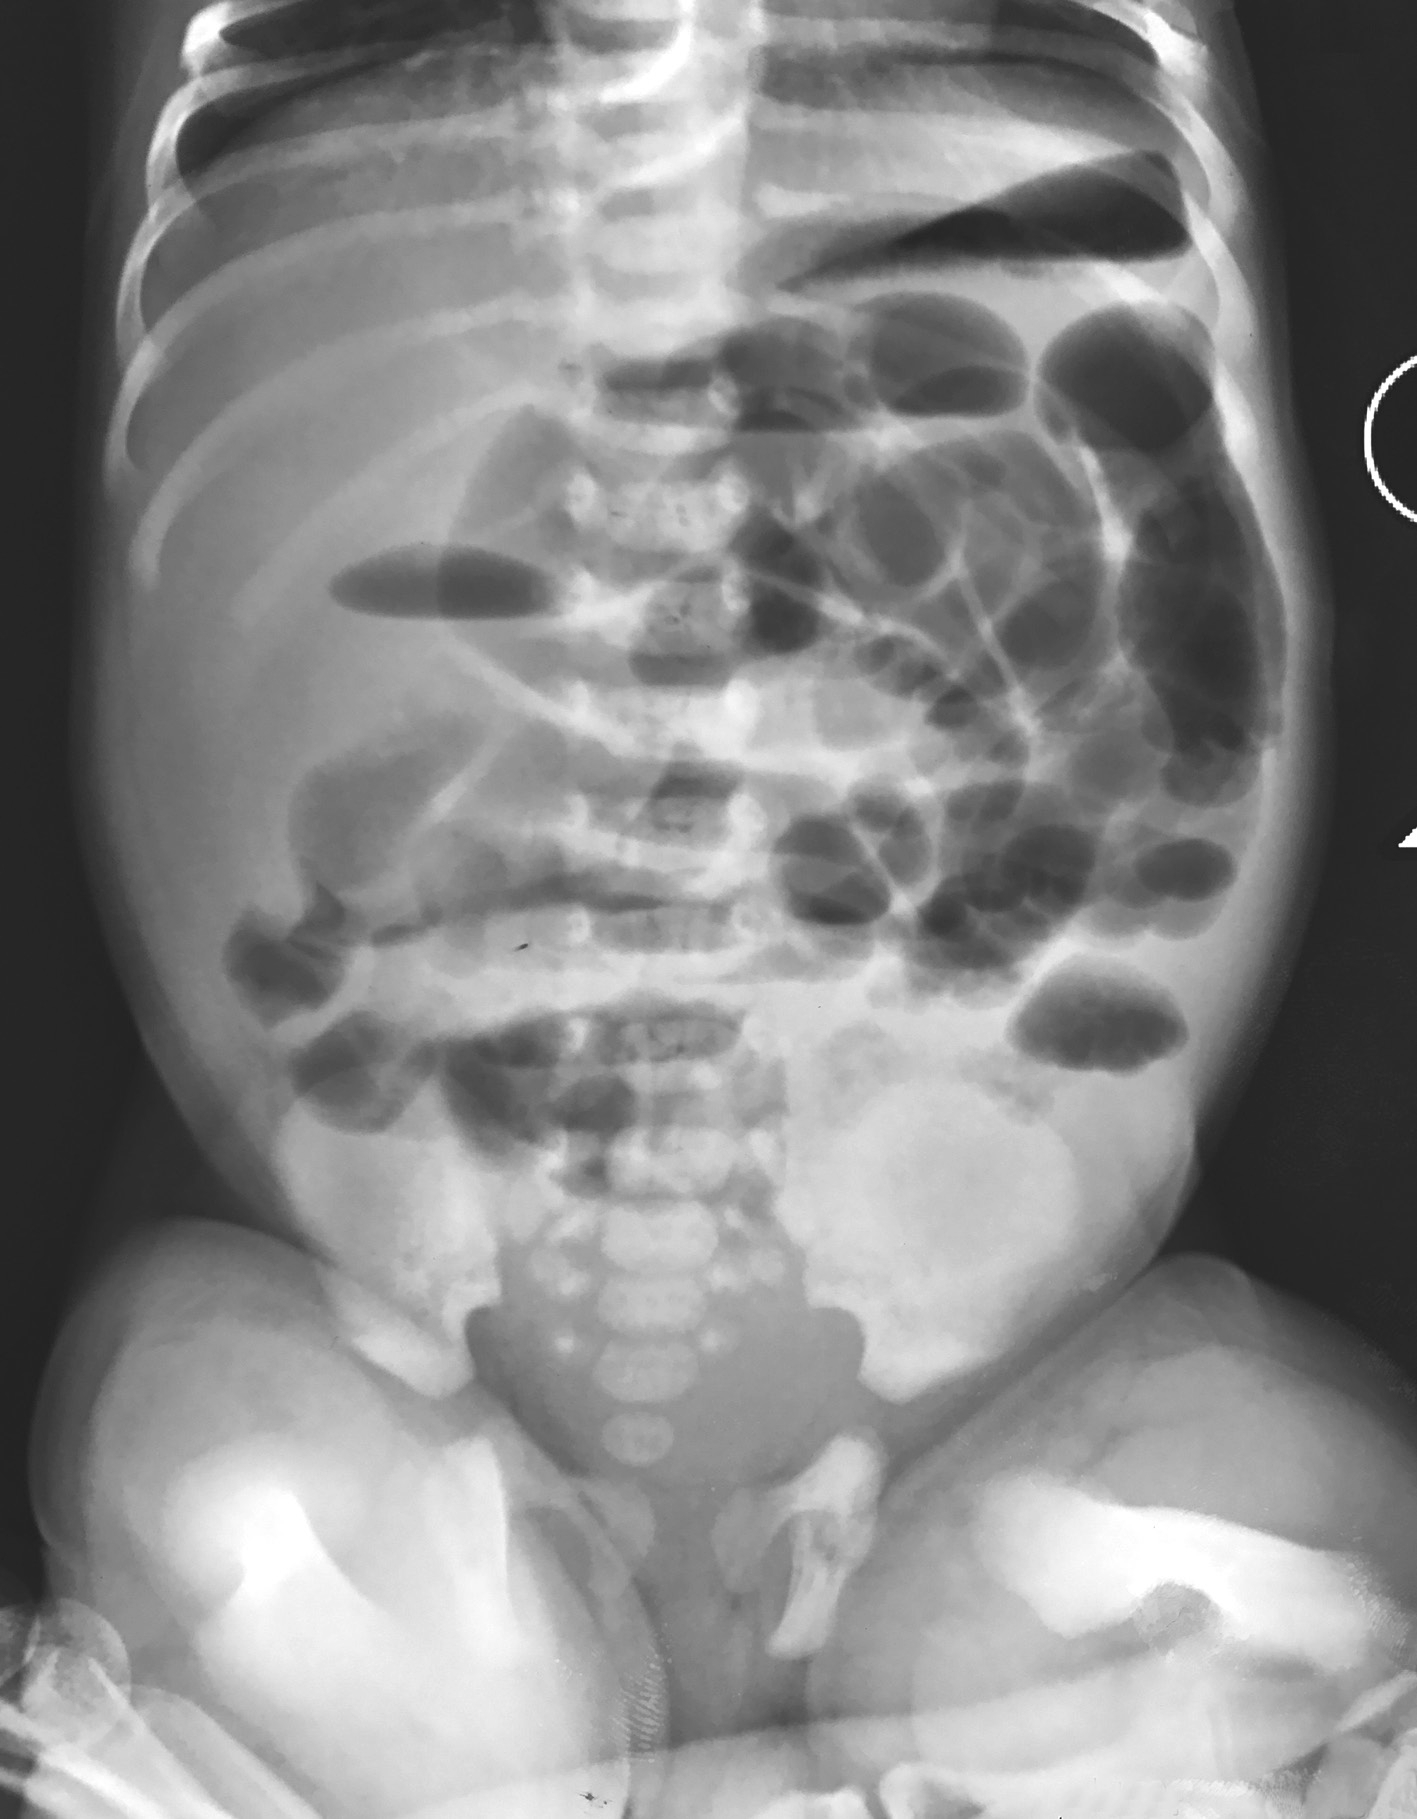

图3-2 新生儿先天性巨结肠症腹部平片

肠管广泛积气,结肠扩张不典型。